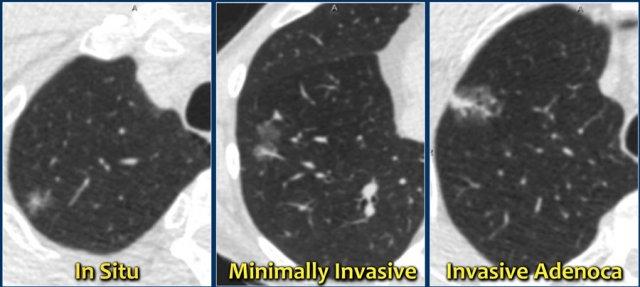

Một phân loại mới dựa trên giải phẫu bệnh cho ung thư biểu mô tuyến đã được giới thiệu vào năm 2011 và phân loại hiện tại này phân biệt giữa:

- Ung thư biểu mô tuyến tại chỗ.

- Ung thư biểu mô tuyến xâm lấn tối thiểu.

- Ung thư biểu mô tuyến xâm lấn.